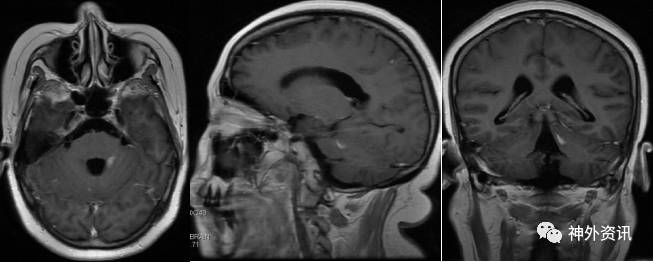

头颅MRI平扫加增强:左侧桥臂异常信号灶,范围约1.0*0.7cm*1.1cm,呈等T1稍长T2信号,增强后强化明显。诊断:左侧桥臂异常强化灶,考虑脱髓鞘病变可能。(图2)。

图2. MRI检查:左侧桥臂异常信号灶,范围约1.0*0.7cm,T1WI呈等信号,T2WI呈稍高信号,增强后明显强化。

入院后神经内科予以脱水、激素及对症支持治疗,患者头痛稍缓解,视力、视野无明显改善。1月后复查头颅MRI增强,提示左侧桥臂病灶无明显变化(图5)。依然考虑左侧桥臂病灶为脱髓鞘病变可能性大。因颅内高压缓解不明显,请我科会诊后转入我科。

图5. MRI复查:左侧桥臂异常信号灶,T1WI呈等信号,T2WI呈稍高信号,增强后明显强化,较前片无明显变化。